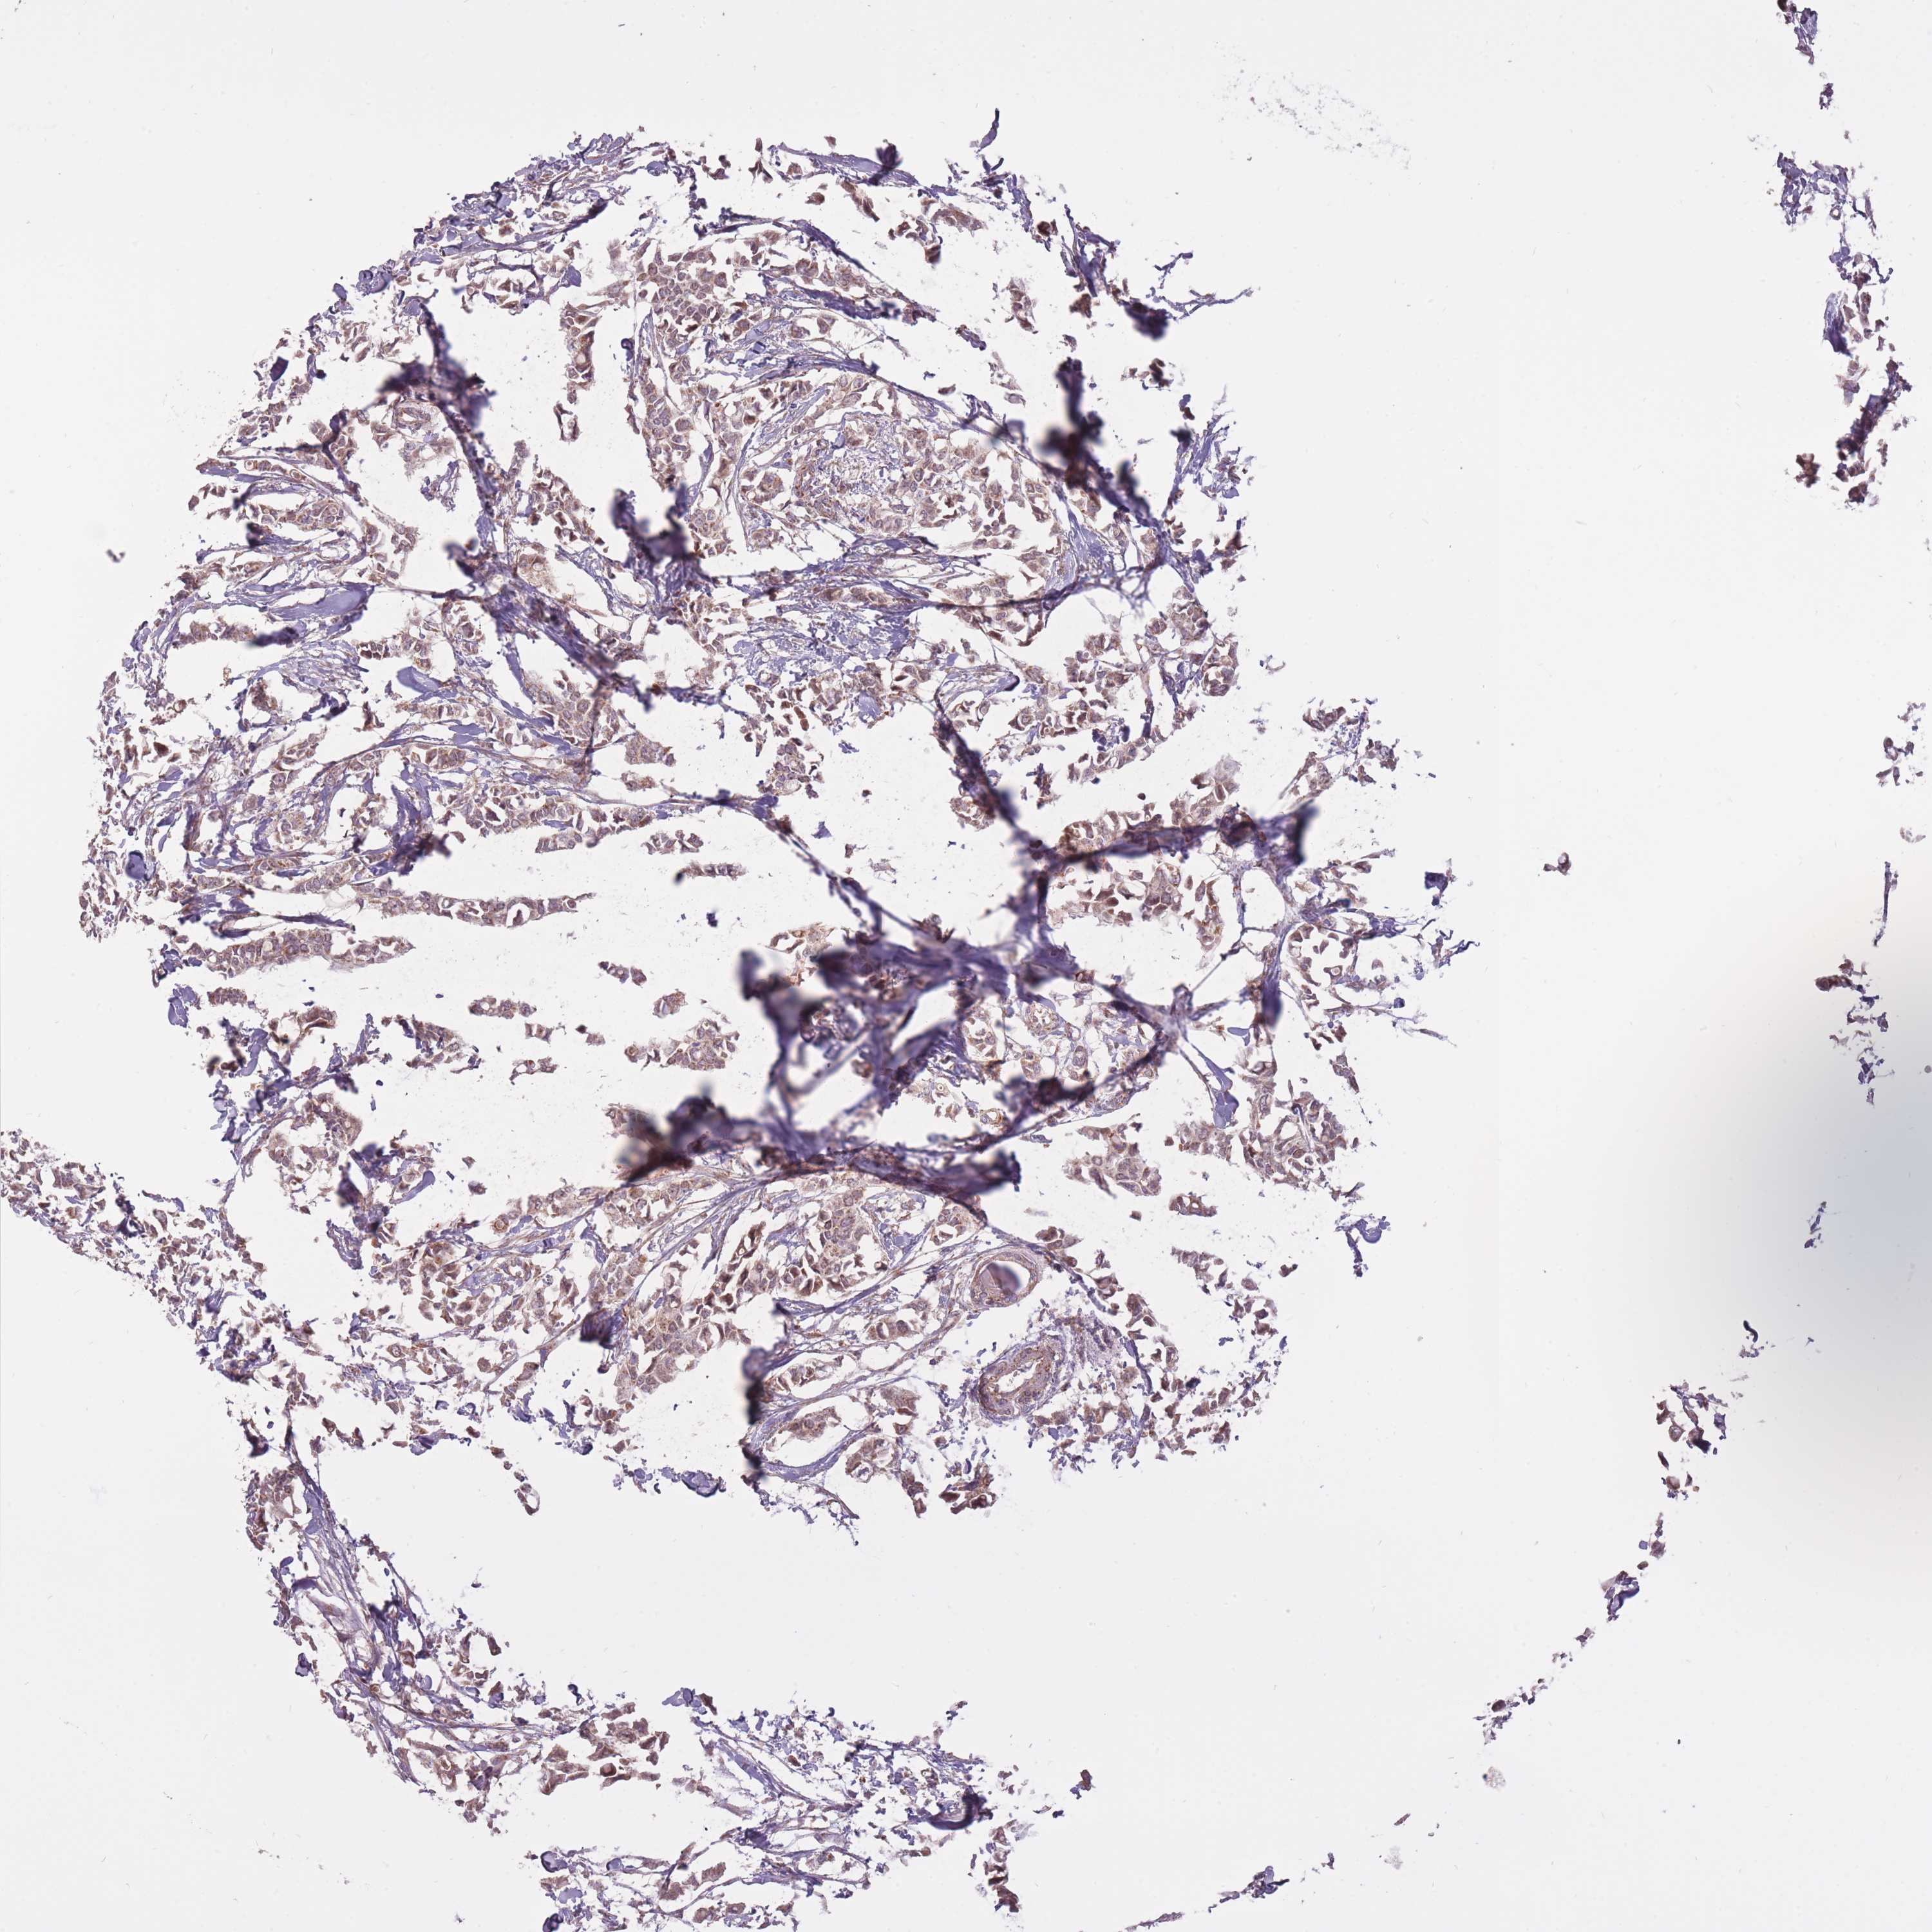

CANCER BREAST CANCER Show tissue menu

BRCA TCGA BRCA VALIDATION PROTEIN EXPRESSION

Breast cancer

Human cancer

LIN7C is not prognostic in Breast Invasive Carcinoma (TCGA)